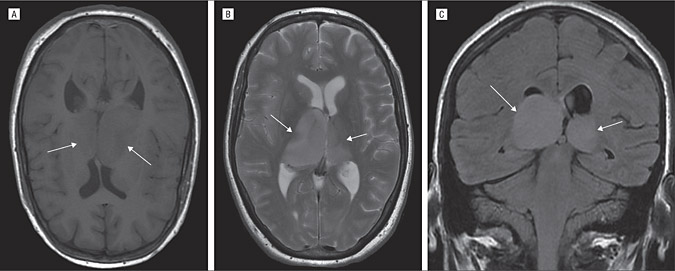

作为钢琴演奏家、钢琴老师的Z女士,大约4个月前发现出右手弹奏不灵活,细致活动限制,头部右侧和右脚麻木感,也偶有视力模糊、有雾感,起初本以为是太劳累所致,却不见好转,当地医院就诊,在当地医院发现丘脑内较大占位,考虑胶质瘤可能。Z女士而后辗转多处,得知德国Helmut Bertalanffy(巴特朗菲,国内病人尊称“巴教授”)在这领域的丰富成功经验,成功联系并进行了二意见咨询,得到可以手术全切的回复后,一家人带她前往巴特朗菲教授所在的德国汉诺威INI国际神经学研究所进行手术治疗。

在5-ALA荧光、术中神经导航和术中MRI辅助手术,通过左侧顶枕枕骨开颅术和显微外科肿瘤全切手术,手术顺利,无手术并发症。患者术后当天即拔出气管插管,无任何问题,转入重症监护室进行观察1天。术后当天与术前相比,右手和手臂仍有轻微的偏瘫和轻度运动无力,无言语功能障碍。术后2天,检查术后CT正常,无血肿和明显脑水肿等,该患者的临床状况迅速好转,并迁出ICU。术后3天即在物理治疗下增加康复锻炼,下地锻炼,术后5天即可自行站立行走。在INI住院期间,手细致功能障碍、言语和感觉偏瘫均得到好转。右手的细致运动技能也比手术后开始时明显好转。